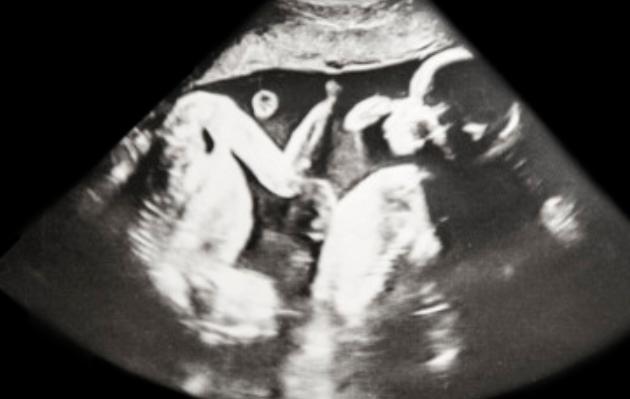

三代试管是一种技术,由精液和卵子转移到宫腔的一种方式,以满足受困者的生育需求。它可以提高夫妻生育的几率,有助于实现夫妻双方的生育愿望。